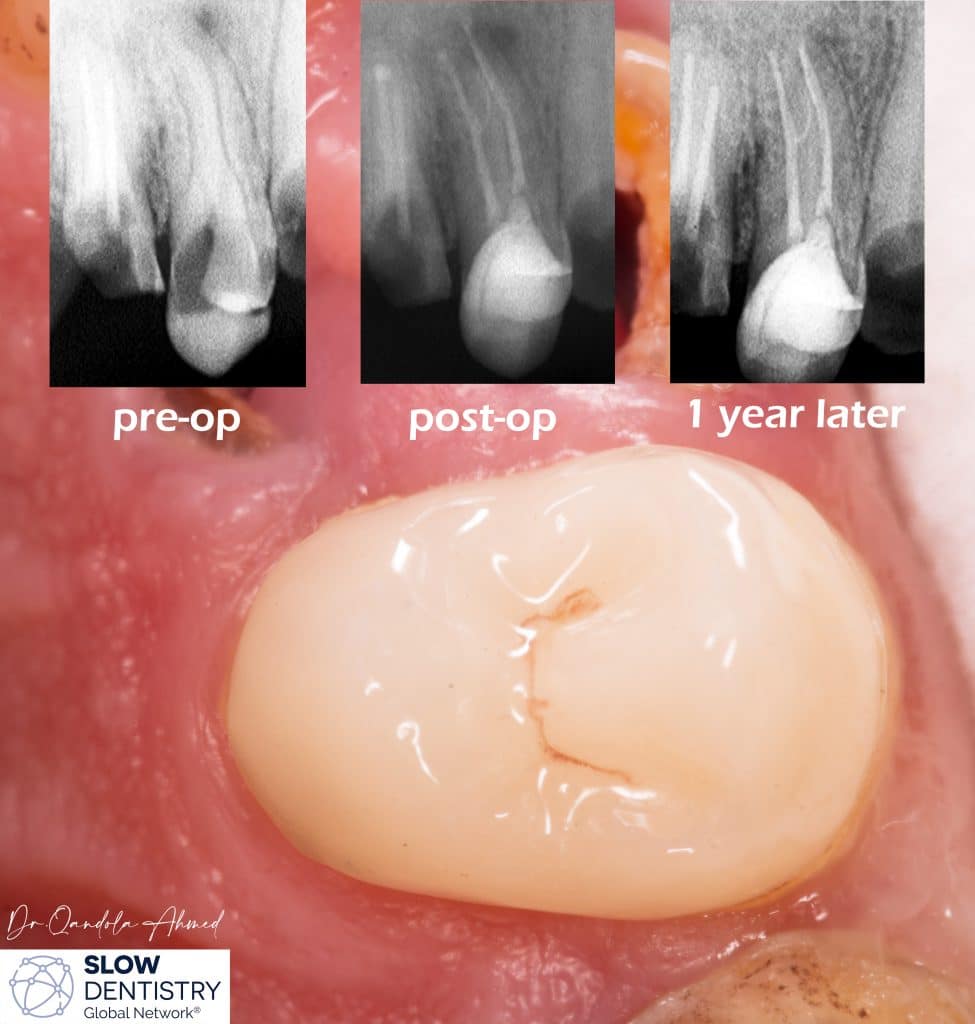

extensive caries criss-cross upper first premolar ,patient came in with severe pain , Radiograph shows a periapical radiolucency .

intracanal medication was placed for 1 week .

Indirect restoration was cemented by heated composite .